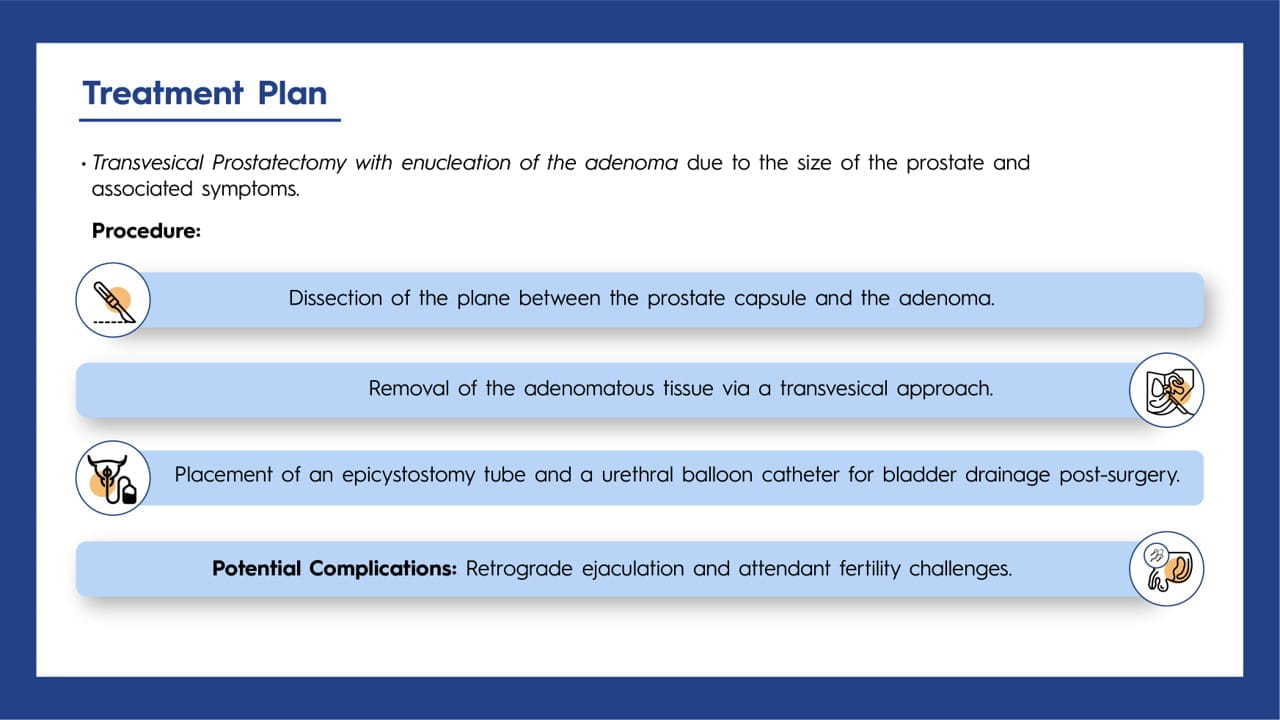

BPH, a common condition in older men, can occasionally progress to giant prostatic hyperplasia, where the prostate gland exceeds 500 g. Surgical options may be considered for complications that are challenging to manage with medication. In this case study, the patient successfully underwent a transvesical prostatectomy to treat a significantly enlarged prostate weighing 600 g.